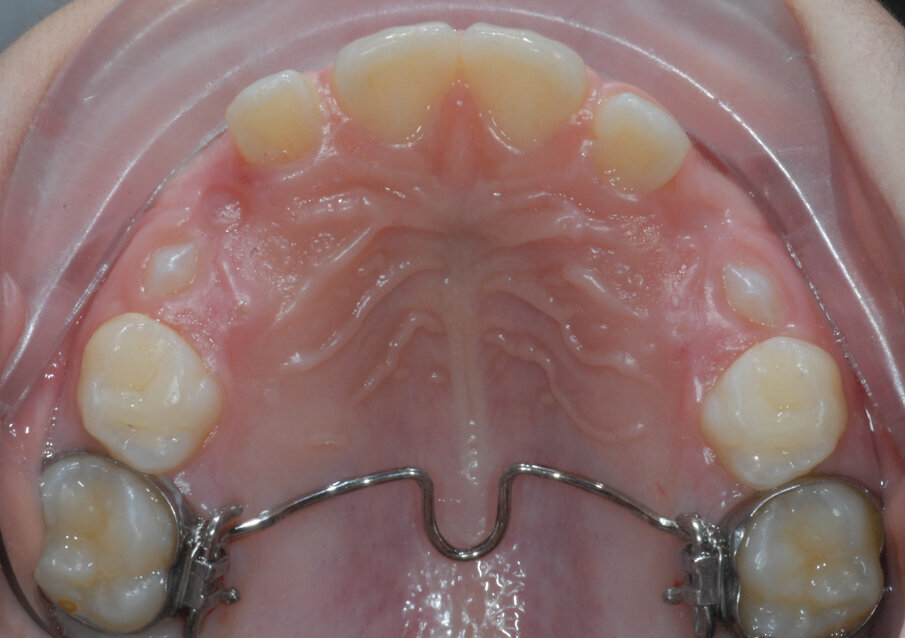

Alessandro, 8 anni, viene sottoposto ad una CBCT (Figg. 21, 22) dopo una valutazione iniziale dove si è riscontrato un percorso di permuta difficile dei canini permanenti (1.3-2.3).

Tramite scansione digitale delle arcate vengono ottenuti dei modelli virtuali, i file .STL vengono inviati al laboratorio ortodontico per la realizzazione di un espansore lento del palato Leaf Expander® (Leone, Sesto Fiorentino (FI), Italia).

Il dispositivo customizzato e prodotto tramite laser sinterizzazione (Fig. 23), viene cementato su “E” e riattivato periodicamente. Dopo la fase di espansione e stabilizzazione (Fig. 24), vengono ottenuti dei nuovi modelli virtuali per la progettazione (Fig. 25) e produzione (Fig. 26) tramite fresatura di una barra di Nance in Trilor® (Bioloren, Seregno, Italia). Alessandro, una volta cementata la barra di Nance (Fig. 27), viene sottoposto ad estrazione anticipata dei canini (5.3-6.3) e dei primi molari decidui (5.4-6.4).

Fig. 24_Leaf expander a 6 mesi.